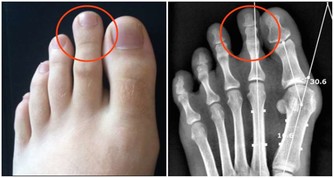

九:護甲雞蛋

健康的指甲是粉紅色的,因為有充足的血液供應。

若指甲變化異常,往往是營養缺乏或其他潛在症狀造成的。

而高蛋白飲食是維持健康指甲所必需的,雞蛋則是獲得蛋白質的良好來源。